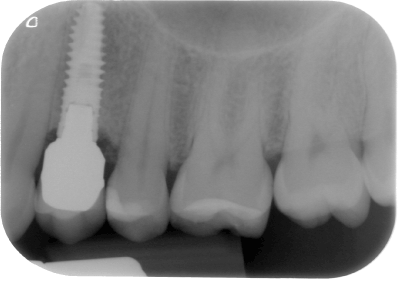

In July 2016, at the last check up visit, 97.3 % of all implants placed were still in situ (Figure 3). Table 5 exhibits the life table analysis for the implants, showing separate survival rates for the maxilla and the mandible (Figure 4). When the survival of implants was evaluated separately for implants with and without additional bone augmentation, the rate was of 97% in implants without additional bone augmentation and 100% in implants with augmentation. The results thus differed insignificantly. A separate data evaluation of implants with additional bone augmentation was not possible due to the small number of cases in each group. A 15-year cumulative survival rate of 97.3 % existed.

Figure 3. Xive S implant at the check up in 2016.